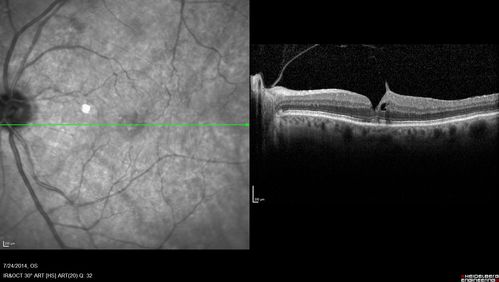

Vitreomacular Traction -> Macular Hole -> Aborted Macular hole

Progression of VMT in both eyes over time